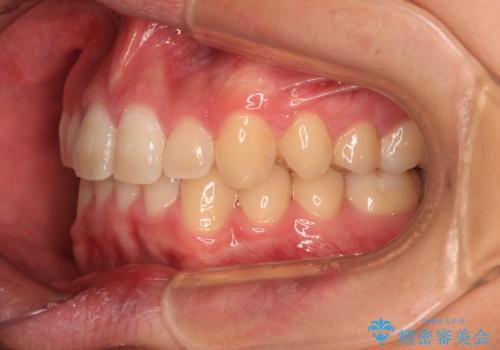

傾斜しいている大臼歯を立ち上げながら、下顎歯列を上顎に対して前方位となるように工夫し、デコボコを解消した上でディープバイトも改善することができました。

- 上下前歯のデコボコと深い咬み合わせを気にして来院された患者様です。

下顎前歯が一本欠損しており、下顎の歯列が小さいため、ディープバイトになりやすい状態でした。